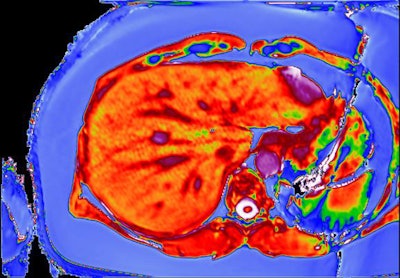

LiverMultiScan images of patient with fatty liver disease before (above) and after (below) bariatric surgery. Based on these scans, it was decided liver biopsy was not needed in this patient. Copyright Perspectum Diagnostics.The study, conducted by researchers at the University of Birmingham and the University of Edinburgh, investigated the performance and cost of multiparametric MRI (LiverMultiScan) alongside existing biomarkers in the assessment of nonalcoholic fatty liver disease (NAFLD). Adult patients undergoing standard-of-care liver biopsy for NAFLD were prospectively recruited at the two U.K. liver centers in Birmingham and Edinburgh, and they underwent multiparametric MRI, blood sampling, and transient elastography within two weeks of liver biopsy. The researchers compared noninvasive markers, with histology as the gold standard.

They found LiverMultiScan in 50 patients and six healthy volunteers was superior for grading disease severity and excluding people at increased risk of disease progression, compared with the other tests evaluated.